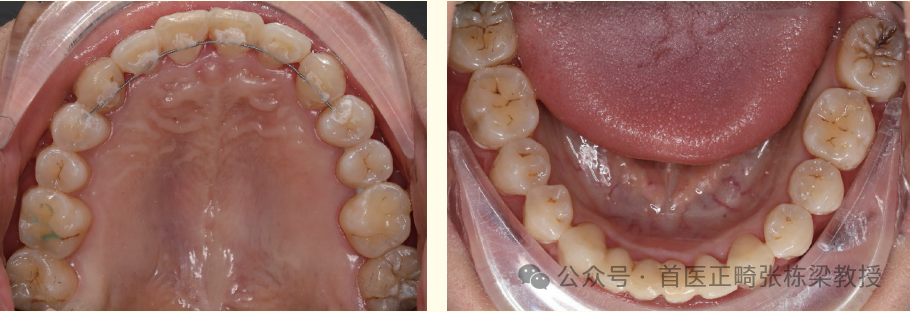

我们使用上下颌种植支抗,远中直立后牙获得间隙,配合必要的片切获得间隙排齐前牙。

但是需要时间,这位女士的牙齿问题解除时间是两年,因此牙齿矫正中需要正畸医生的信心和患者的耐心。

当然每个人牙齿情况不同,深覆合的严重程度不同,所选择的打开咬合方式也会不同,需要正畸医生实际评估确定适合自己的正畸方案。